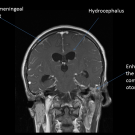

A 31-year-old previously healthy woman was admitted to the hospital for a 5-day history of bloody diarrhea and associated epigastric abdominal pain. She reported having a fever, with a maximum temperature...